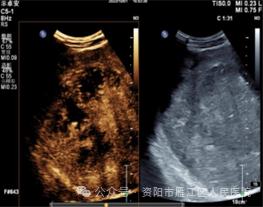

近日,56岁的李大叔因“右上腹疼痛20+天”入住我院。入院后查腹部增强CT:肝脏内结节、团块状稍低密度影,考虑肿瘤性病变。遂请超声科会诊, 腹部普通肝脏彩超提示:肝右叶实性占位,考虑肿瘤性病变可能。

超声造影:肝右叶实性占位性病变,考虑肝细胞Ca可能性大。

为进一步明确肝右叶病变的病理类型,遂行超声引导下肝肿物穿刺活检:

穿刺过程十分顺利,术后患者恢复良好,无明显不适症状。穿刺活检术后病理结果:考虑为低分化肝细胞癌(WHO III级)。为制定下一步治疗方案提供了重要依据。